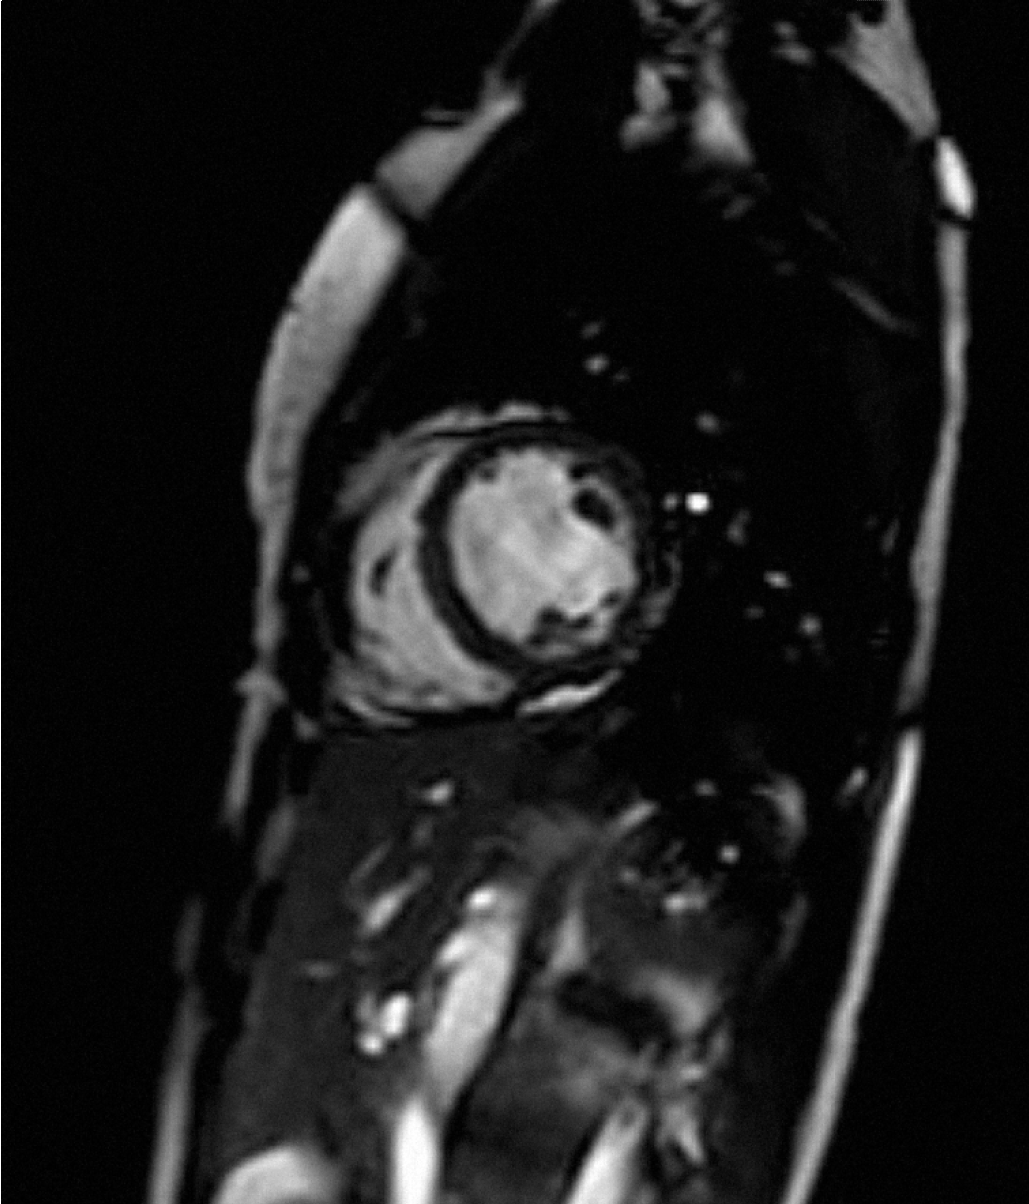

A 51-year-old Caucasian female with a past medical history of depression underwent dental procedure. She had no allergy, no history of smoking or alcohol consumption, and no family history of heart disease. The dentist injected a solution of 2% xylocaine into gum. Three minutes following the procedure, the patient complained for chest pain, during one hour. She was admitted to a cardiac intensive care unit. Her blood pressure was 125/65 mmHg, her pulse rate was 70 beats per minute (regular), and her spontaneous arterial oxygen saturation was 97%. Her physical examination was normal. Her electrocardiogram (ECG) revealed T waves inversions in AVF, DII, DIII, V4, V5 and V6 (Figure 1). Troponin level performed at admission was 23 ng/mL (N=0,05). C-reactive protein (CRP) concentration was normal. Chest X-ray was normal. Cardiac catheterization and ventriculography were normal. An early trans-thoracic echocardiogram and cardiac MRI found a global left ventricular hypokinesis with depressed ejection fraction of 40%, without late gadolinium enhancement (Figure 2)

(Figure 3) (Figure 4). Chest pain stopped the first day and the patient was discharged from hospital six days later, with beta blocker treatment (bisoprolol 5 mg/day). Left ventricular ejection fraction has been checked normal (65%) after five weeks of treatment. We concluded to atypical TTC induced by injection of xylocaine.